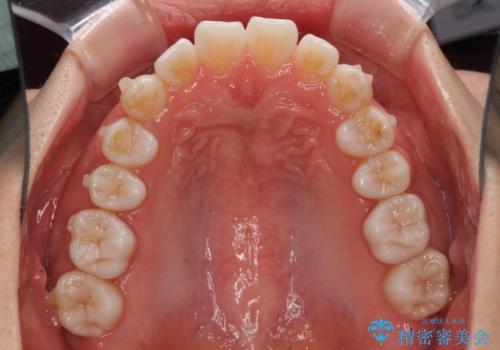

インビザラインによる軽度な出っ歯の矯正治療

- 上の前歯の出っ歯を治したいとのことで来院された患者様です。

上下顎ともにIPR(歯と歯の間を削る)と歯列全体の拡大によって口元が引っ込むように設計し、インビザラインにより治療を行うこととしました。

どこまで口元を引っ込めることができるのか、患者様自身も正直分からない部分があったため、少しずつ治療ゴールを変更しながら仕上げていきました。

気になっていた前歯の飛び出した印象は、最終的にはスッキリと引っ込み、大変満足していただきました。